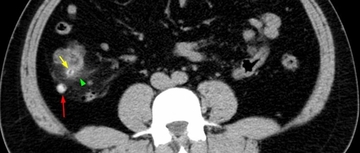

小心误诊,这可不是急性阑尾炎!

#盲肠憩室炎

2026.03.19

694浏览